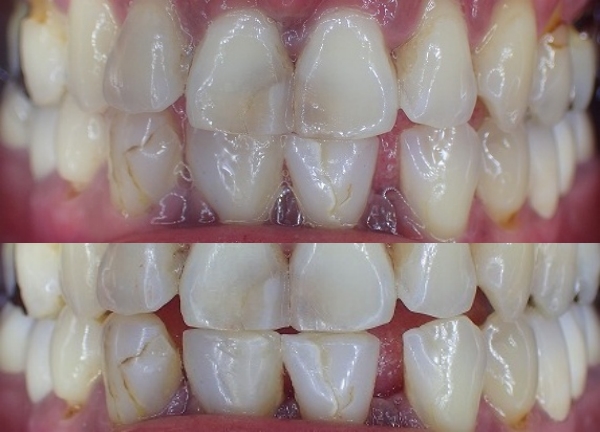

上が本来あるべき咬み合わせ

下が奥歯がないので前歯の上下で咬む習慣

歯の切端が削れています。

この場合は大きくレジン充填がしてありますので

これ以上レジン充填をすると、歯が崩壊するリスクが

高くなると思われます。

下顎前歯の形態修正前 修正後の比較

上が形態修正前

下が形態修正後